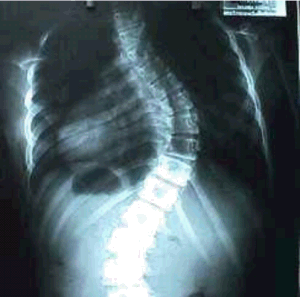

LA ESCOLIOSIS. Se le llama así a una curvatura anormal lateral de la columna vertebral, ya sea hacia la izquierda, o hacia la derecha de su eje central (ver figura 1). Esta curvatura está acompañada de una rotación de las vértebras afectadas.

Figura 1. Apariencia de la escoliosis

Las costillas sufren rotación e inclinación que deforman la caja del tórax y pueden llevar al diagnostico antes de que se presenten las curvaturas lumbares (ver figura 3). Las costillas de la concavidad, rotan y se hacen horizontales además de desplazarse hacia delante y las de la convexidad se hacen hacia atrás, agudizan el ángulo y se hacen verticales. La mitad del tórax correspondiente a la convexidad disminuye su capacidad, el esternón se desplaza y el tórax se descentra.

Figura 3. Radiografía de tórax, donde se observan costillas horizontales (lado izquierdo de la imagen), y verticales (lado derecho), las curvaturas anormales y graves de la escoliosis, disminución de la capacidad pulmonar y el acuñamiento de los cuerpos vertebrales en los puntos de curvatura máxima. Tórax descentrado.